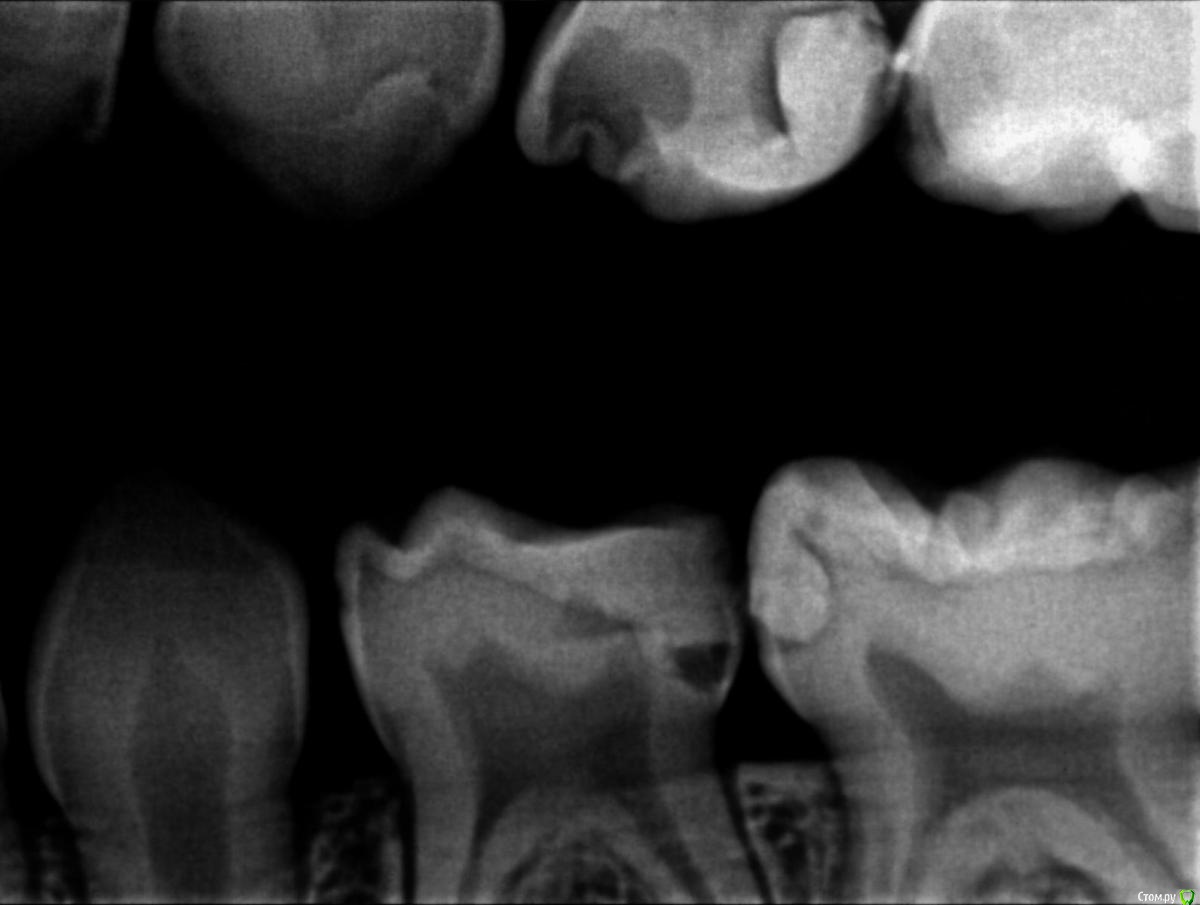

Пошли к врачу, сделали рентген и на рентгене видно что начал образовываться кариес почти на всех молярах, либо под пломбами, либо на стыке зубов. Так как зубы уже леченые доктор говорит что лечить дальше смысла нет, пломба держаться не будет, выпадет снова, предлагают ставить коронки сразу на все моляры, а зуб где уже большая пломба (зуб I на ренгене) просто удалить (не болит) и поставить space mantainer + удалить зуб А.

Зуб А - он депульпирован, лечили в апреле, там есть абсцесс (шишка над десной), дали антибиотик пока и приговорили на удаление. Другой врач правда говорит, что в его практике он такие зубы не рекомендует удалять сразу, т.к. свиду абсцесс не похож что связан с кариесом по ренгену и возможно вызван прорезывающимся следующим зубом. Предлагает пропить антибиотик и посмотреть что будет - если опять воспалиться, то тогда уже удалять. А пока наблюдать. Т.к. удаление этого зуба сейчас принесет большие проблемы потом, ввиду того что space mantainer туда поставить не возможно пока не выйдет полностью следующий зуб. И как минимум дотянуть до следующего зуба чтобы он вылез правильно, а уже потом удалять.

- надо удалять нерв (или верхнюю часть нерва). Странно это делать на зубе который не болит. Даже если молочный зуб просто год но с нервом это помоему лучше. Зубы S, J, L  - удаление нерва под коронку, I - тоже, если зуб сохранять. Остальные зубы просто закатывают в коронки без удаления нерва чтобы не возвращаться к этому вопросу через год.

На всякий случае прикрепляю снимки, буду рад услышать мнение.